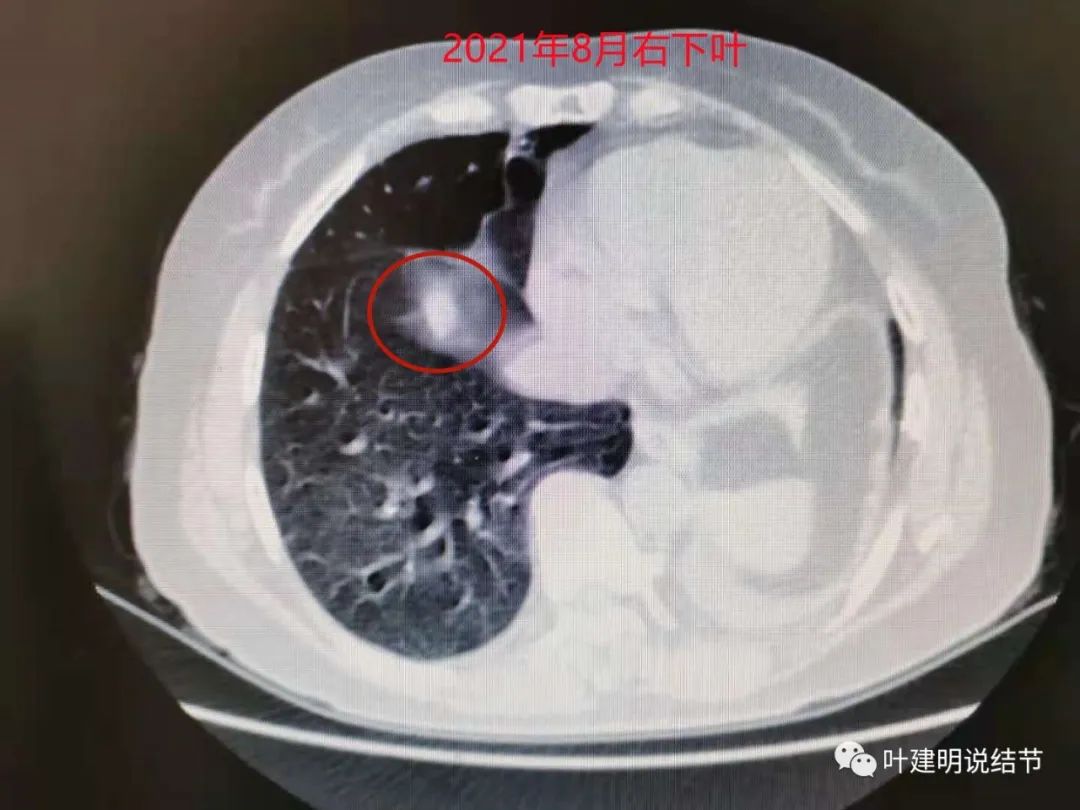

这是最近一次平扫的片子,此结节感觉有膨胀感,边界较清,位于肺底,贴膈面。我们从数次复查的对比,看来该结节是缓慢进展的,不吸收也不钙化,也不是纤维增生或条索状瘢痕的样子。在门诊我仔细对比了这些不同时间的片子后,认为右下这结节也极可能是恶性的,该干预。所以我们进一步查了靶扫描: